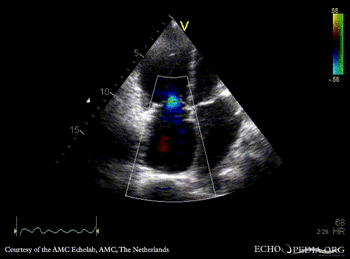

Cor triatriatum dextra

A4CH: Cor triatriatum dextra A4CH: Color Doppler: moderate tricuspid regurgitation